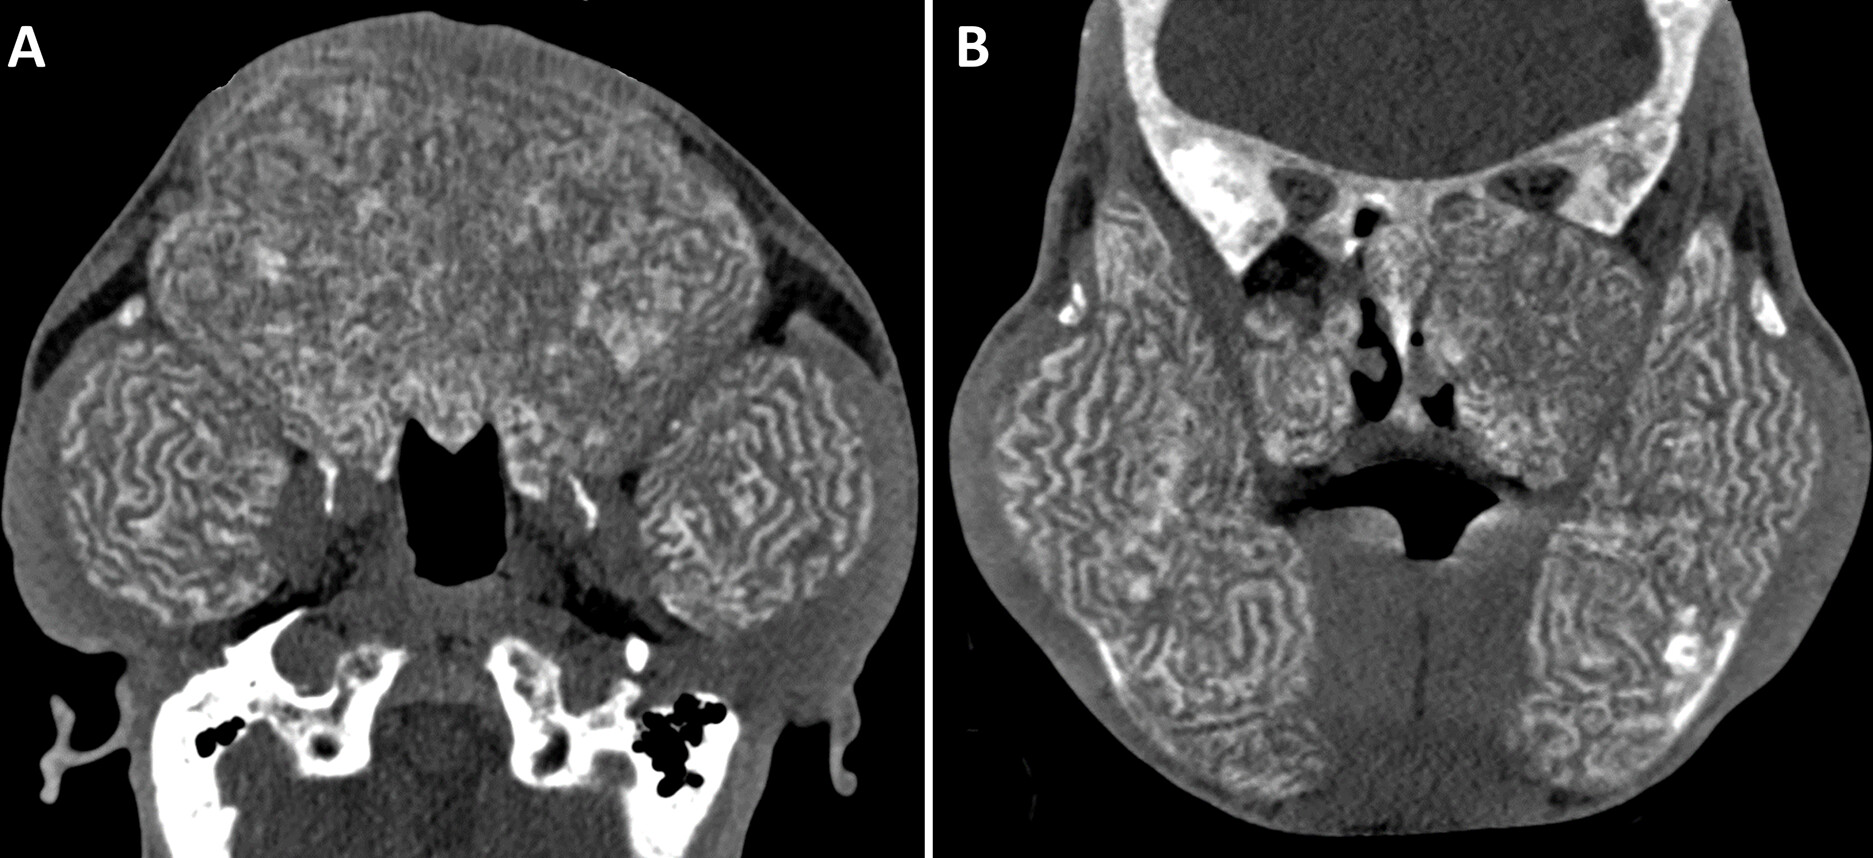

• 尿毒症性狮面症(Uremic Leontiasis Ossea)是一种由于慢性肾病引起的面部骨骼改变,特征性表现为上下颌骨的对称性肥大。

• 该病症的典型影像学特征包括内部蜿蜒的隧道和皮质骨吸收,这些特征有助于与其他类似疾病如纤维性骨炎、Paget病等进行区分。

• 面部CT显示了明显的上下颌骨巨大畸形,这种模式被称为狮面症,因为其类似于狮子的面容。

• 骨结构内部出现了蜿蜒的隧道和皮质吸收,这是尿毒症性狮面症的特征,与患者的风险因素一致。